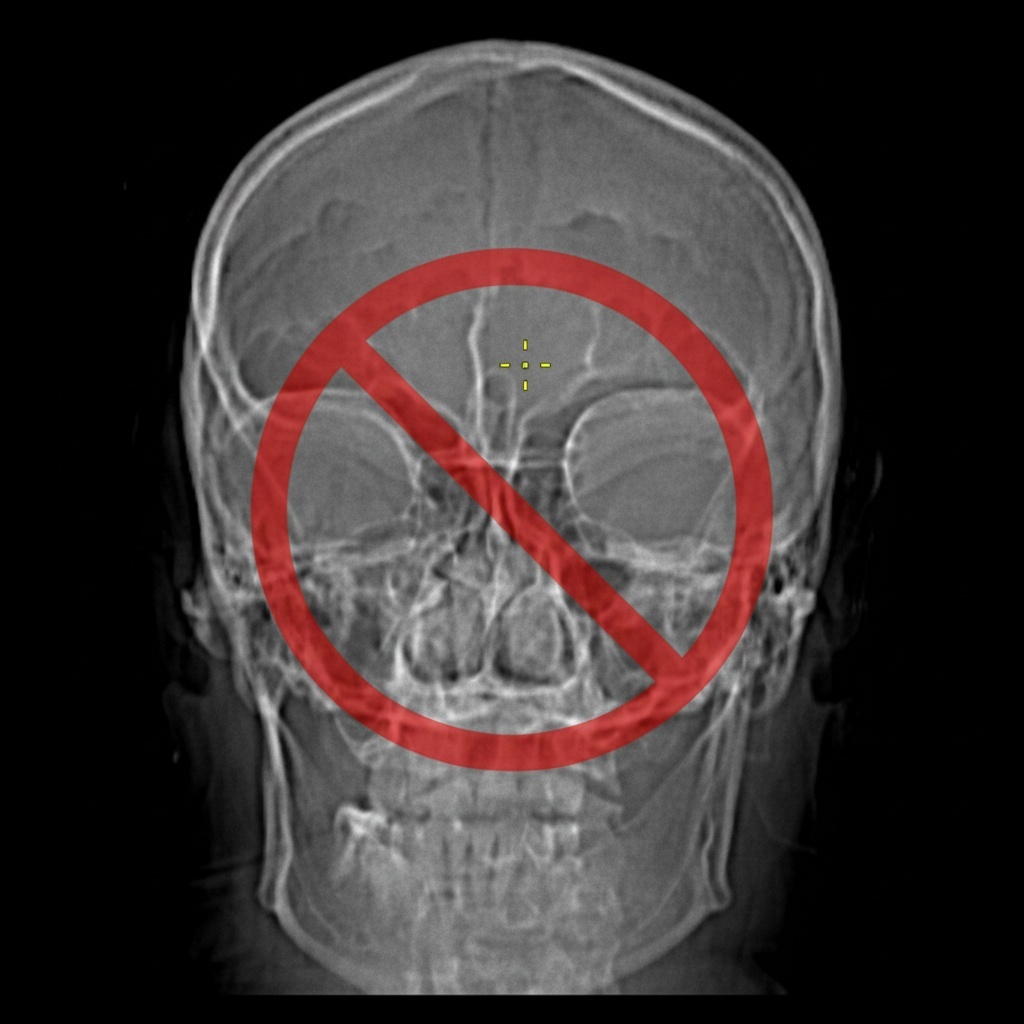

Почему я никогда не рекомендую делать рентген околоносовых пазух своим пациентам?

Ко мне нередко приходят пациенты с рентгеном пазух. Давайте разберемся, почему рентгенография околоносовых пазух — это устаревший метод диагностики, который я, и многие другие ЛОР-врачи, практически не используют в своей практике.

Почему рентген считается устаревшим методом?

Крайне низкая точность диагностики

Согласно официальным клиническим рекомендациям Министерства здравоохранения РФ, данные рентгенографии и КТ околоносовых пазух совпадают только в 34% случаев! Представляете? Это означает, что в 2 из 3 случаев рентген дает неточную информацию!

Для верхнечелюстной пазухи этот показатель чуть выше — 77%, но все равно недостаточен для качественной диагностики.

Неспособность оценить важные параметры

Рентген НЕ позволяет:

🚫 Точно определить степень утолщения слизистой (менее 2 мм)

🚫 Оценить состояние решетчатых пазух

🚫 Визуализировать анатомические особенности

🚫 Выявить ранние стадии воспалительного процесса

🚫 Отличить катаральное воспаление от гнойного